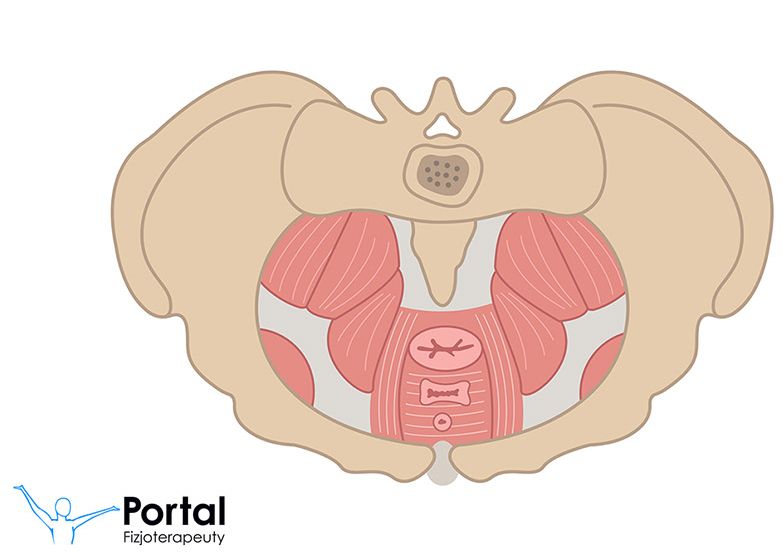

Ostatnio bardzo dużo się mówi o mięśniach DNA MIEDNICY.

(zaznaczone kolorem czerwonym)

Dno miednicy obejmuje 7 mięśni tzw. Mięśnie Kegla od nazwiska uczonego, który już bardzo, bardzo dawno zachęcał do ćwiczeń tych mięśni.

Mięśnie rozciągają się od spojenia łonowego do odbytu. Otaczają cewkę moczową, odbytnicę, ujście pęcherza moczowego oraz wypełniają okolicę narządów rodnych.

Aby poczuć działanie tych mięśni – najprościej to zrobić w toalecie. Wystarczy wstrzymać strumień moczu. Ćwiczenia ich jednak powinny odbywać się poza toaletą, aby nie zaburzać czynności biologicznie funkcjonalnych w naszym ciele.

Ćwiczenia tych mięśni np. Jadąc samochodem powodują wzrost ukrwienia tkanek miękkich w ich rejonie. Poprawia się tu także elastyczność tkanek dzięki temu nie dochodzi do zaburzeń funkcjonowania np. Układu wydalniczego.

Ćwiczenia te są wsaniałe podczas 2 etapu porodu kiedy parcie jest bardzo świadome oraz zaraz po porodzie kiedy mięśnie doprowadzają do wielu powikłań.

Ćwiczenie tych mięśni, to także jedna składowa z leczenia niewysiłkowego nietrzymania moczu zalecana również dla panów, nie tylko dla pań.